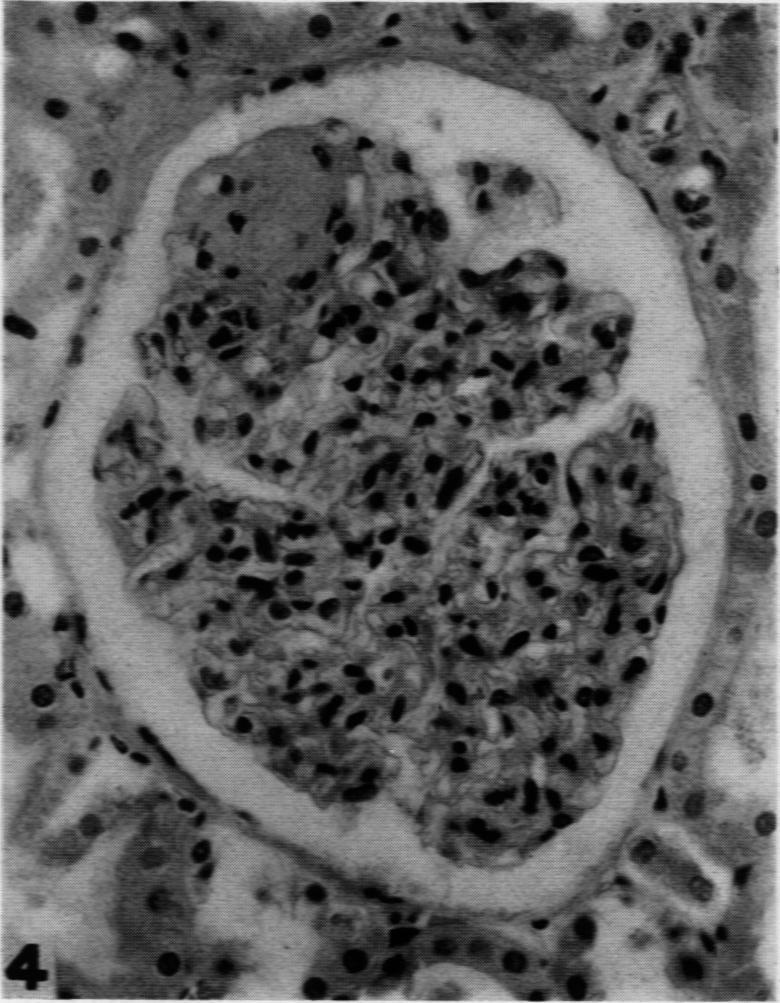

Intercapillary Glomerulosclerosis.

Am J Pathol. 1942 Jan;18(1):93-9.